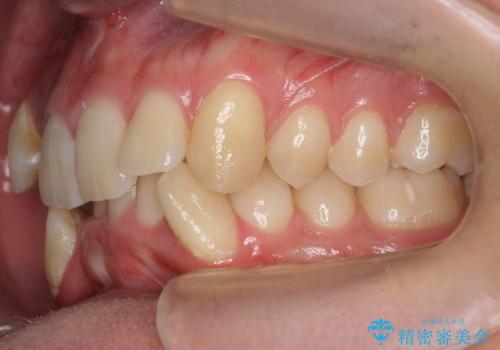

上下の前歯の重なりが大きく(過蓋咬合)時間がかかりましたが、しっかり浅く仕上げることができました。

矯正をしてよかったと大変喜んでおられました。